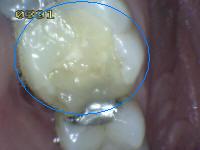

2 |

Sellador completo |